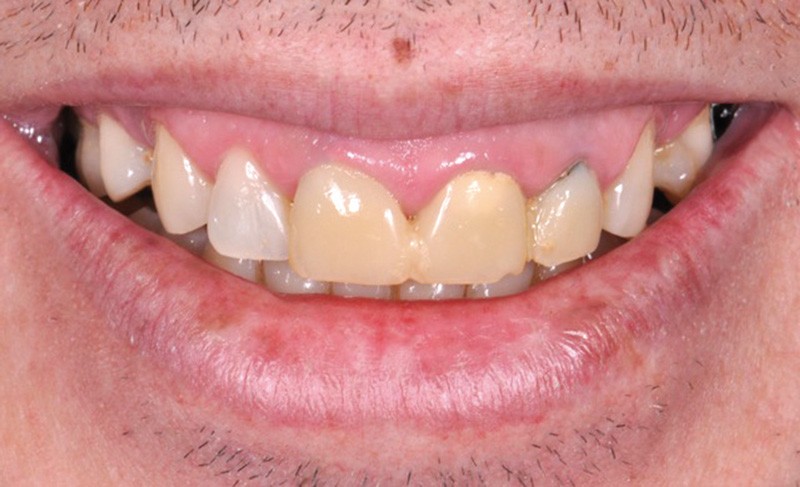

Dans la zone antérieure maxillaire, l’approche esthétique du diagnostic est essentielle (fig. 2a). En effet, la première impression d’un individu est souvent fondée sur ce que l’on perçoit de son visage. Le regard et le sourire constituent les deux pôles attractifs de ce dernier. À distance sociale (et non au fauteuil), ils focalisent toute notre attention et communiquent tous les types d’émotions, verbales et non verbales, de notre interlocuteur. À ce titre, le sourire et le rire représentent la première exposition de l’esthétique dentaire au sein du visage. L’harmonie du sourire est toujours plaisante si l’ensemble des compositions, labiales, dentaires et gingivales, sont agréables au sein du visage des patients.

De nombreuses circonstances nuisent à l’harmonie dento-gingivale des arcades dentaires lors du sourire et représentent un véritable défi esthétique (fig. 2a).